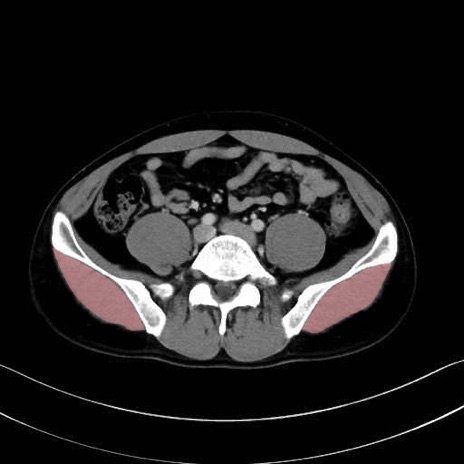

大殿筋 (Gluteus maximus)